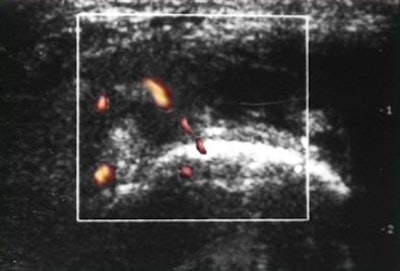

![]() |

| PDS reveals normal vascularity. |

| PDS shows markedly increased vascularity. |